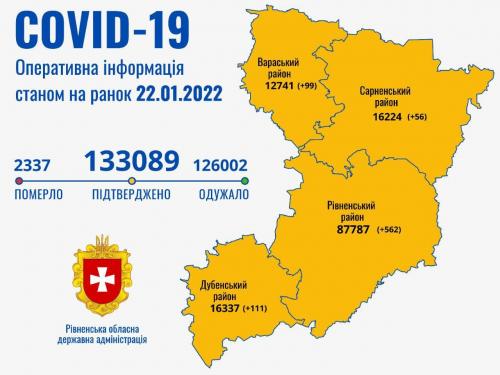

Пів тисячі - у важкому стані, 9 жителів Рівненщини померли за добу від коронавірусу